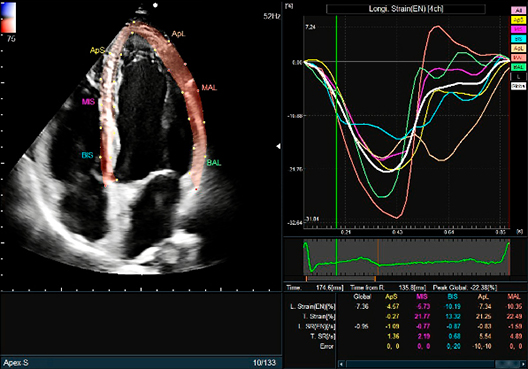

Conducts various measurements via the 2D tracking method fully automatically.

One of them, Global Longitudinal Strain (GLS), is attracting attention in heart failure examinations.